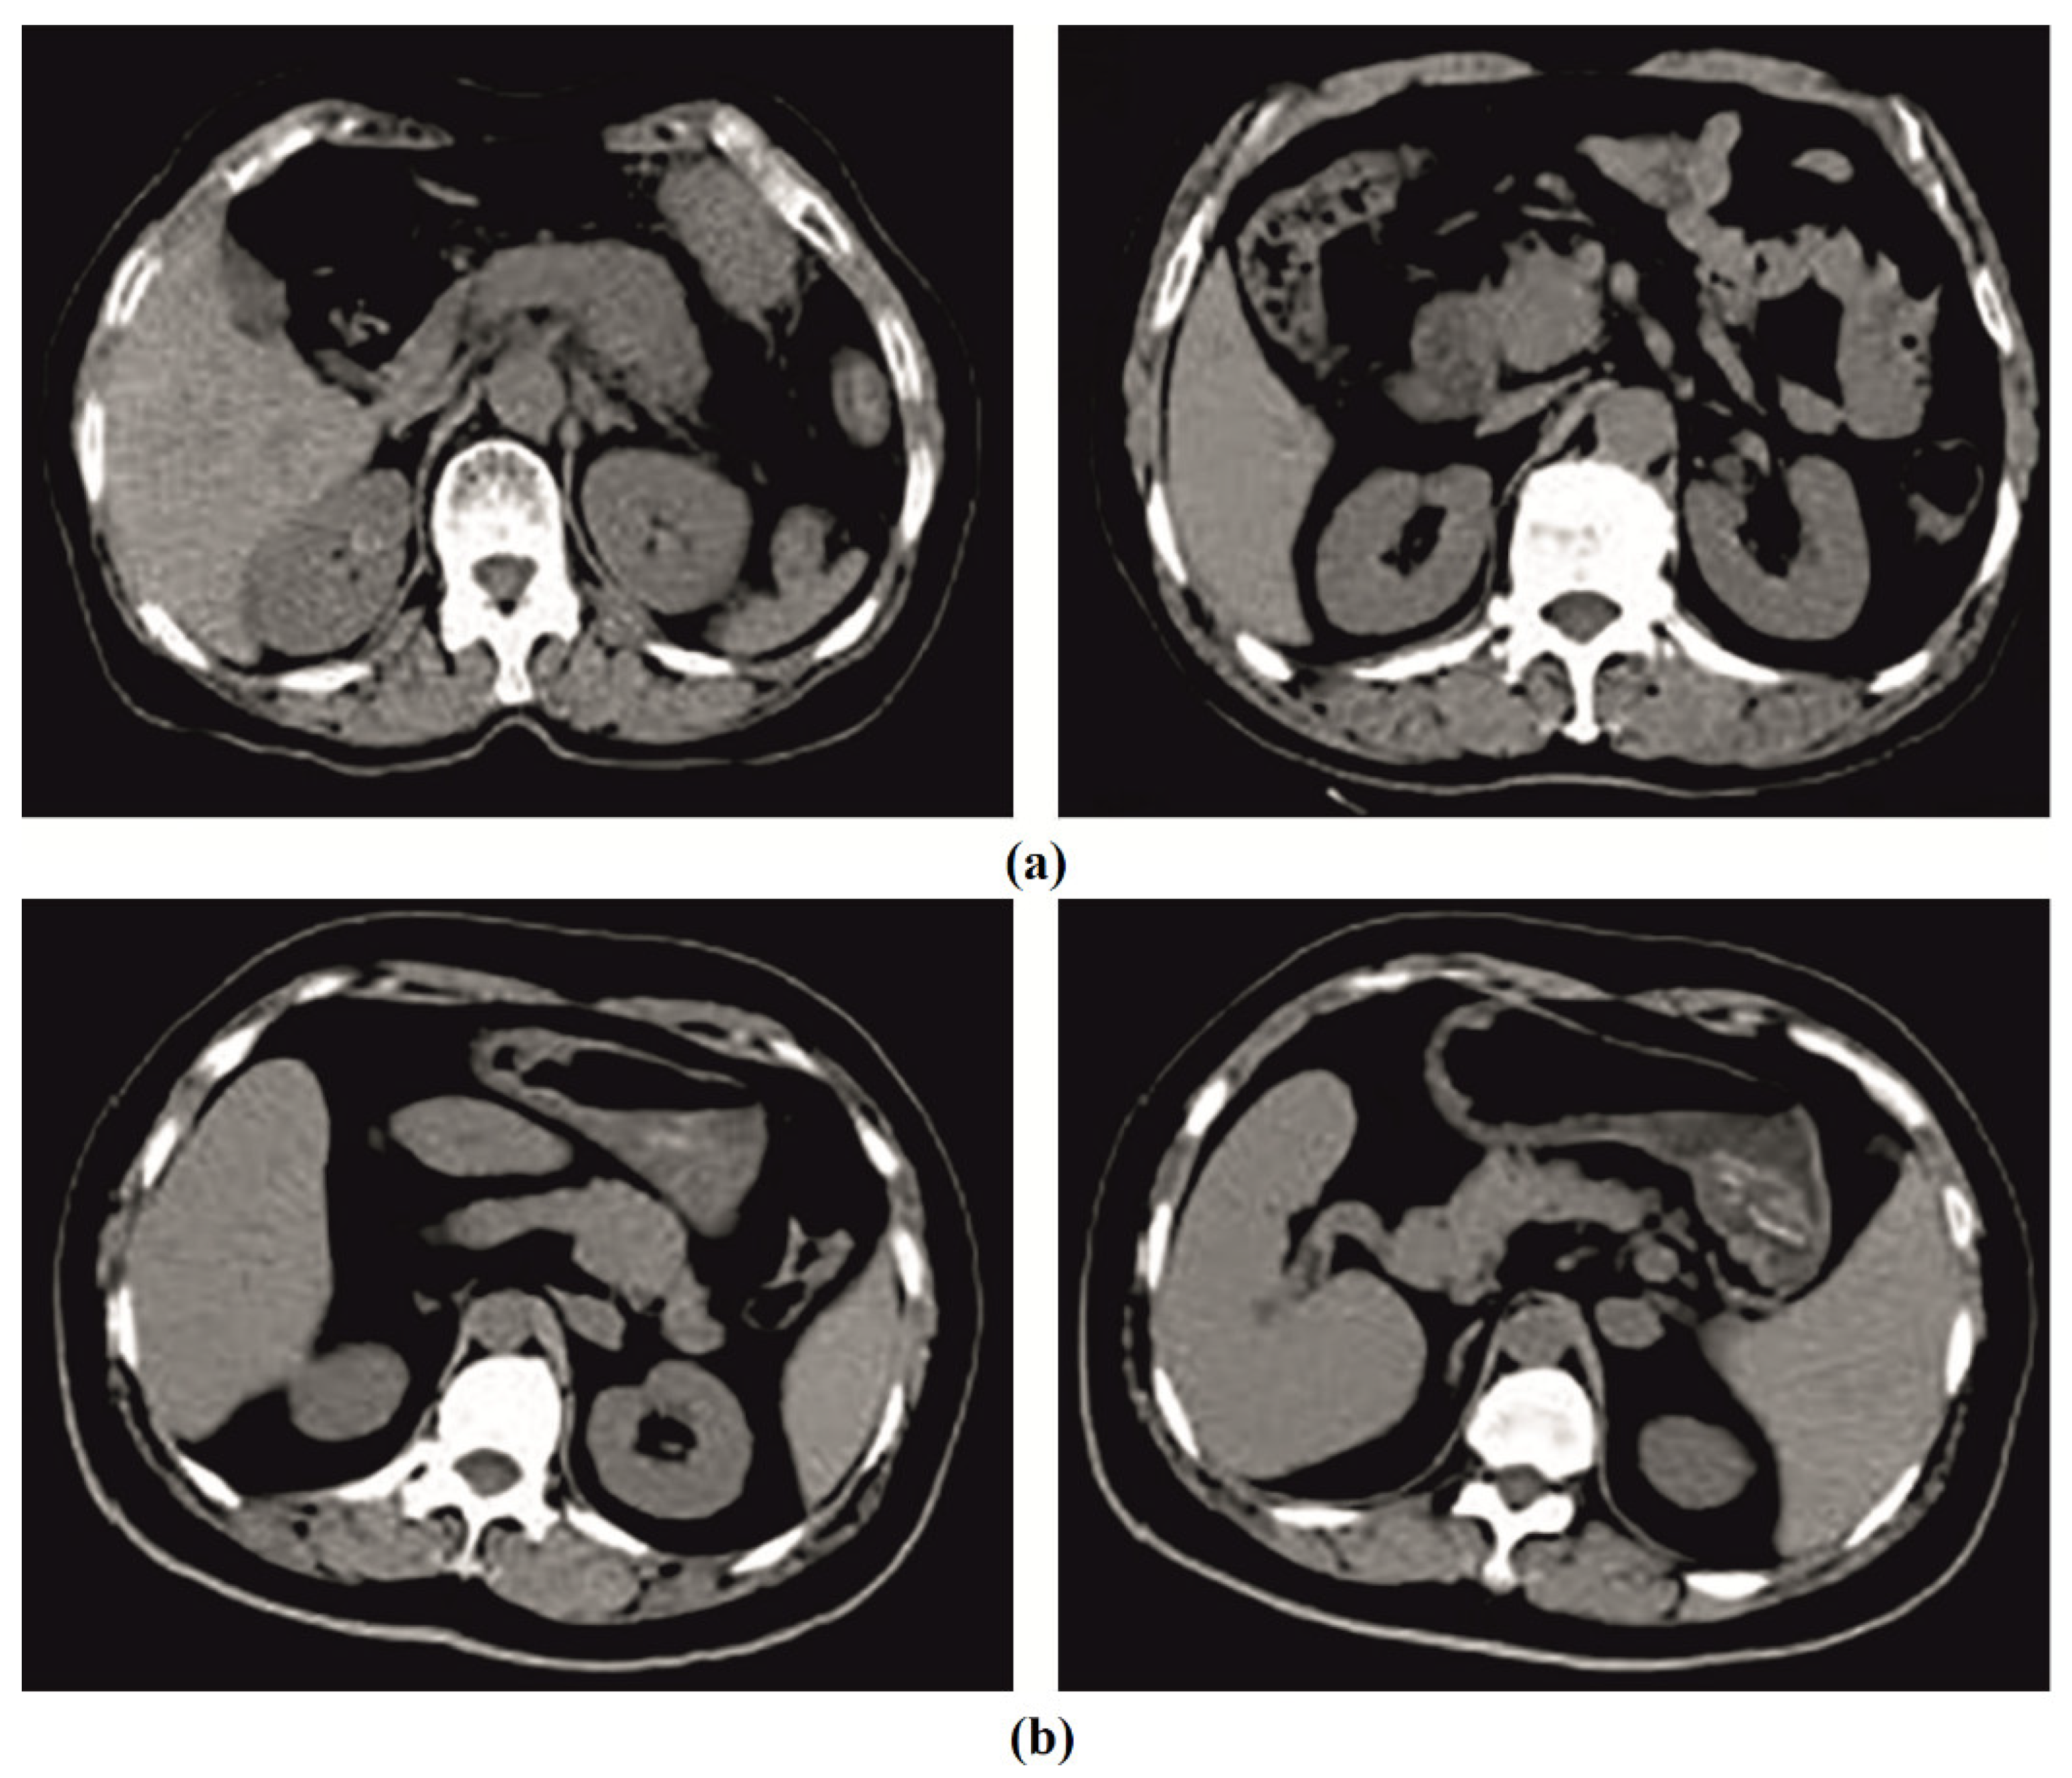

Intelligent Deep-Learning-Enabled Decision-Making Medical System for Pancreatic Tumor Classification on CT Images

4.1. Results Analysis